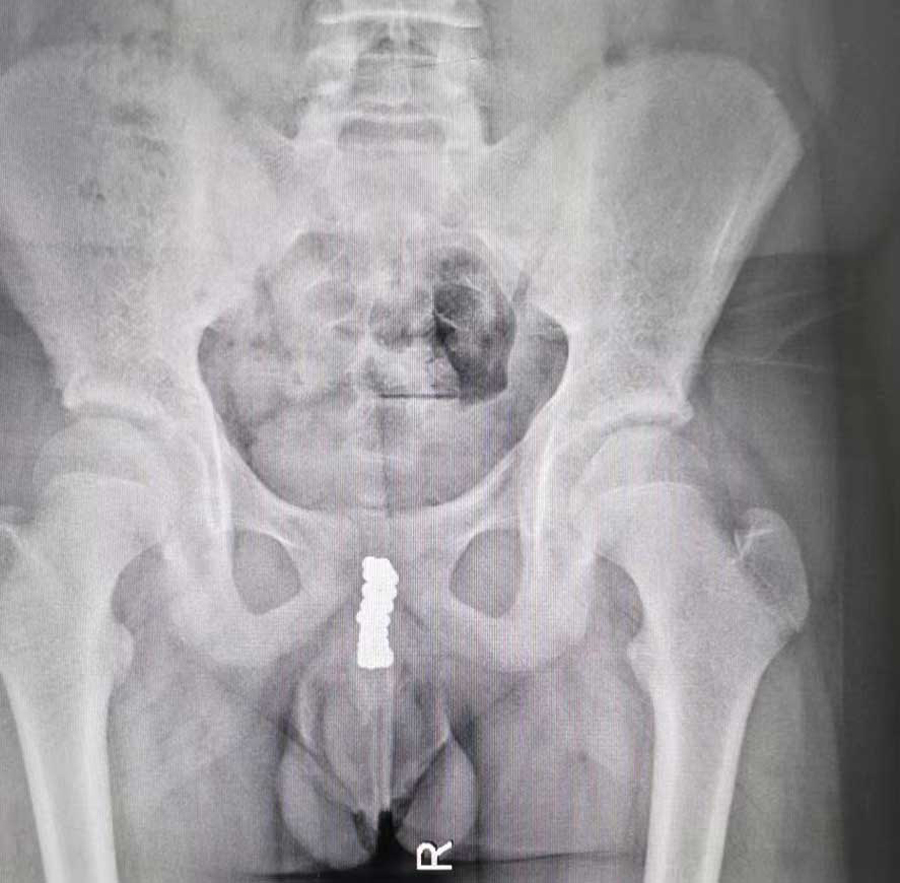

病例1:膀胱、尿道取出近50颗磁力珠

“孩子说把磁力珠塞进尿道里了。”家长一句话让在场人大吃一惊。果然,医生查体时,在小宇会阴区域摸到了珠子。CT检查同样证实尿道内有珠子样的异物,并且吸附在一起。在医生的追问下,小宇才满眼含泪地说了实话。原来,出于好奇,他趁家长不注意,将磁力珠一颗一颗塞进尿道口,并没告诉家长,等出现排尿疼痛、血尿后,才不得不跟家长说起。由于磁力珠位于后尿道膜部位置,所以医生从后尿道位置剖开,手术取出10余颗磁力珠。术中,C型臂透视显示,膀胱内还有一团磁力珠,医生通过下腹部耻骨联合上的切口,将膀胱打开,又取出30多颗磁力珠。手术前后近3个小时,共取出近50颗磁力珠。由于磁力珠在尿道及膀胱内的长时间吸附,取出时附着着脓性分泌物,说明尿道内已经感染了。